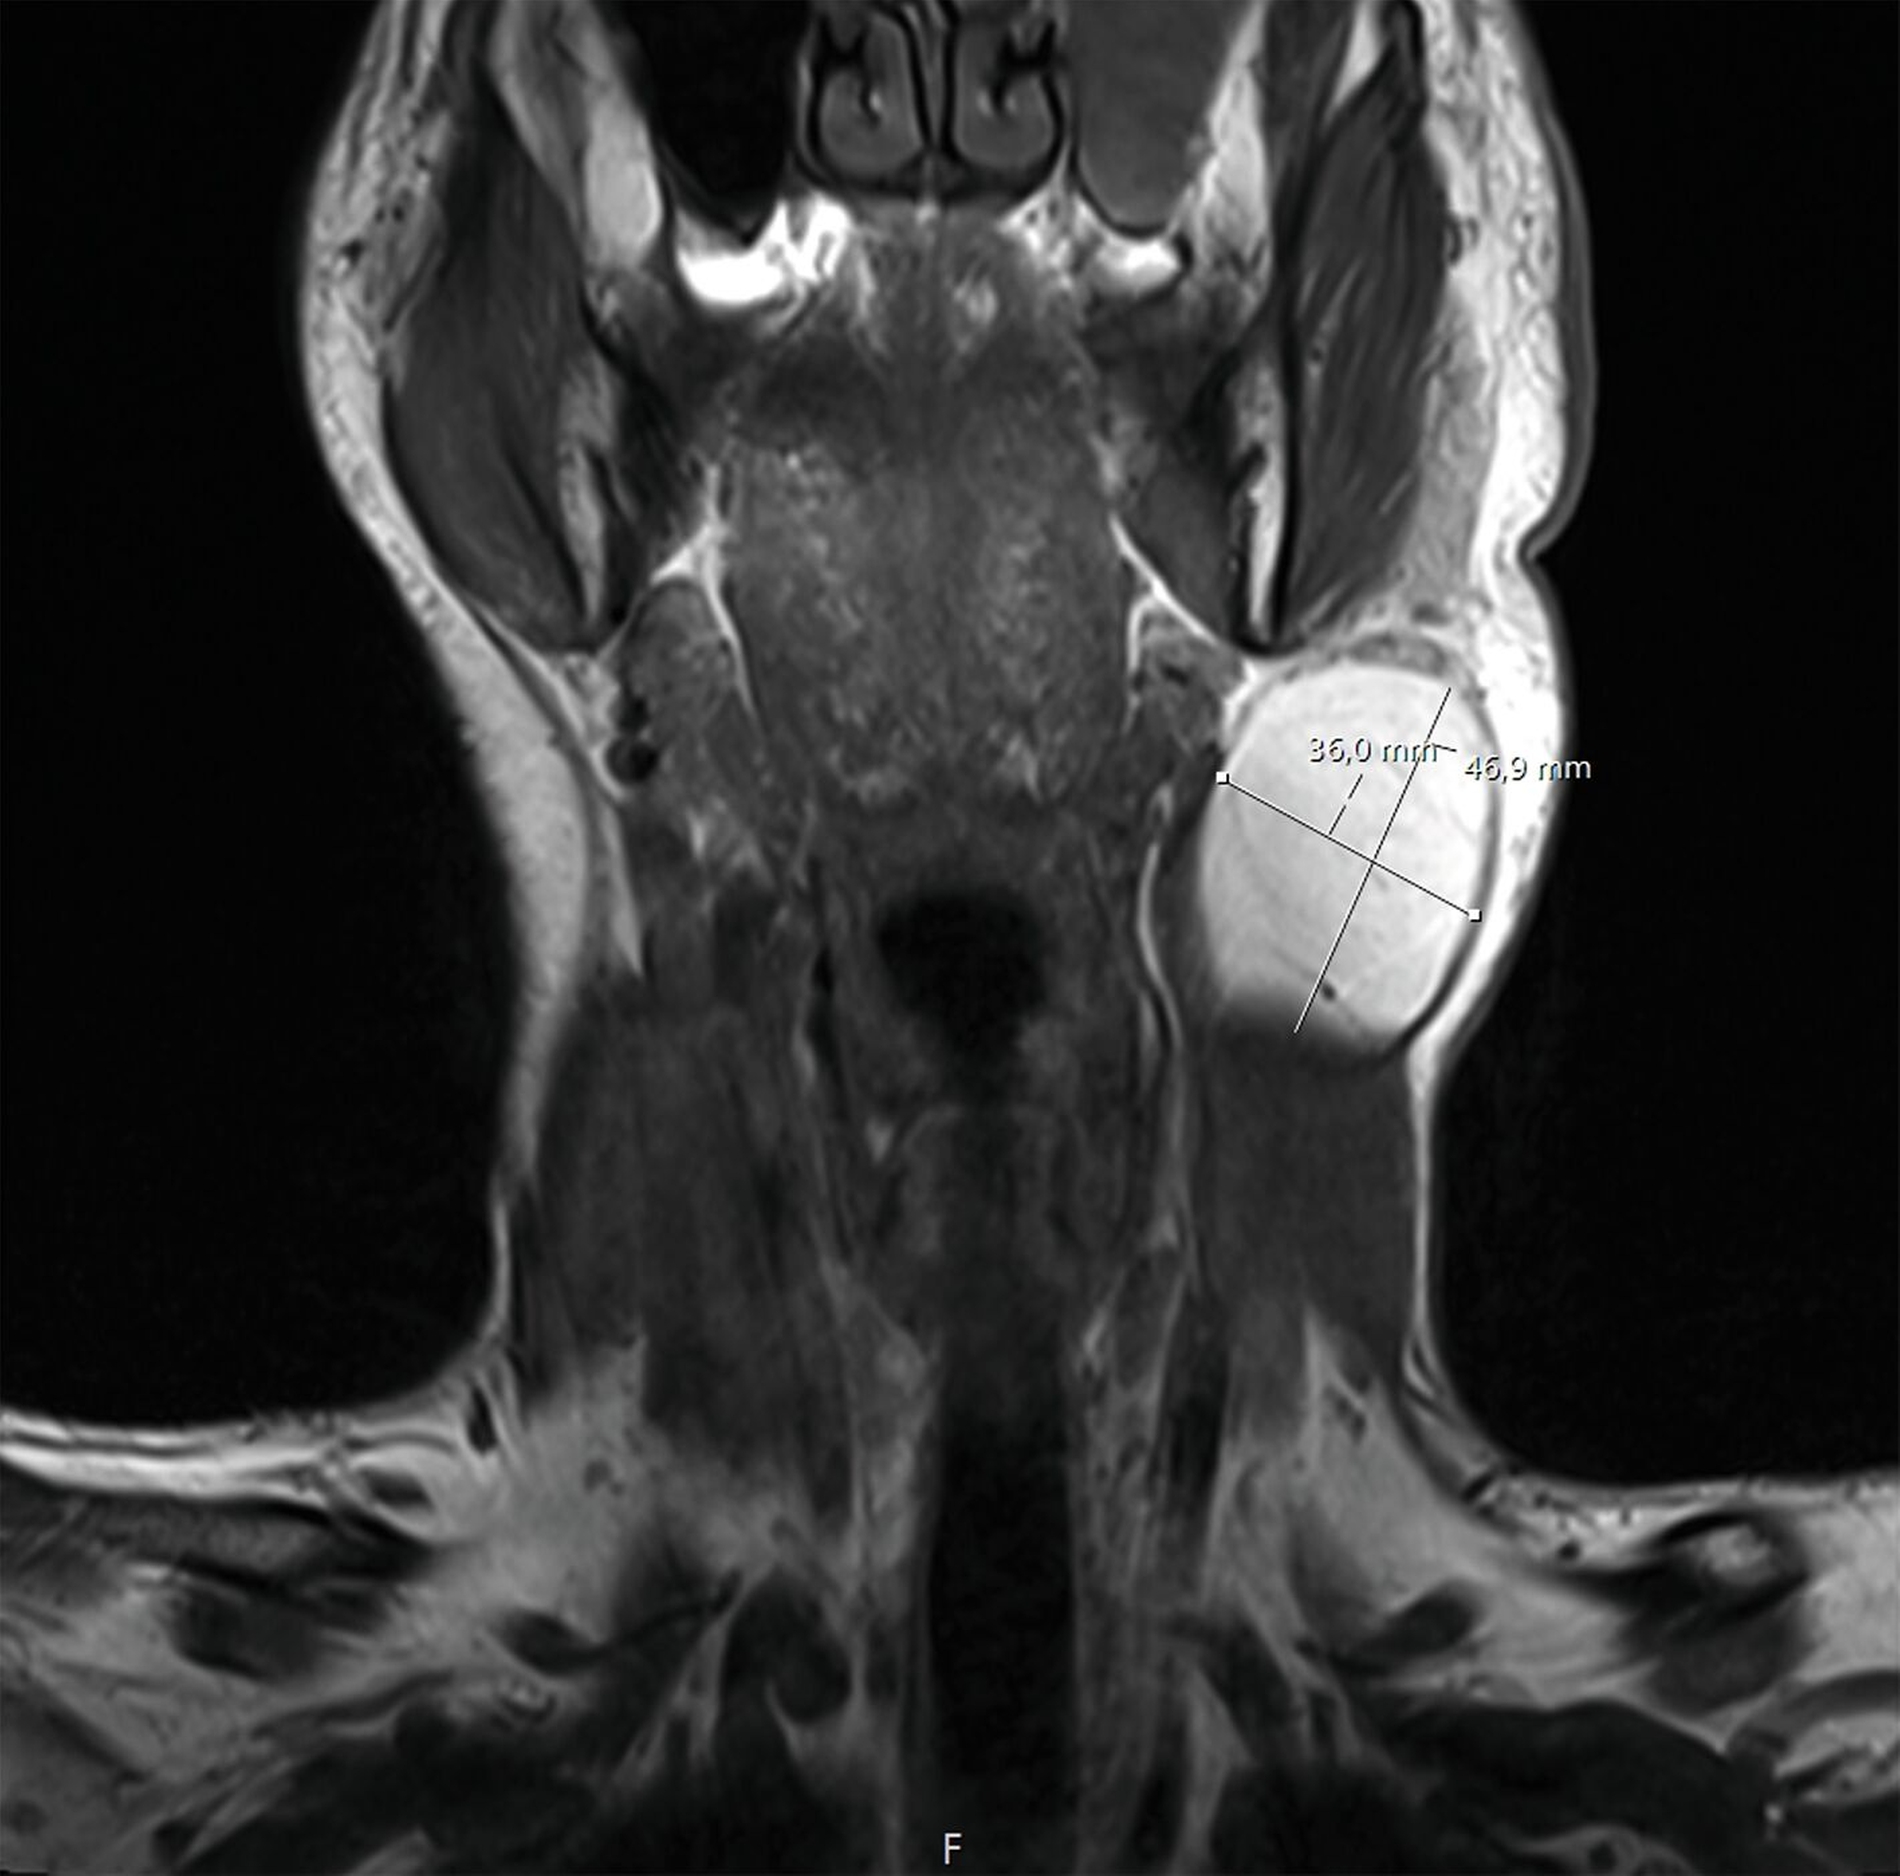

Eine radiologische Verlaufskontrolle mittels Magnetresonanztomografie brachte eine deutliche Volumenzunahme der bereits bekannten Raumforderung zur Darstellung. Es imponierte eine Größe von 36 mm x 47 mm in Kombination mit einer vorangeschrittenen Verdrängungstendenz im Bereich der zervikalen Muskulatur (Abbildung 3). Darauf folgte die Überweisung des Patienten zur weiteren Therapieübernahme.